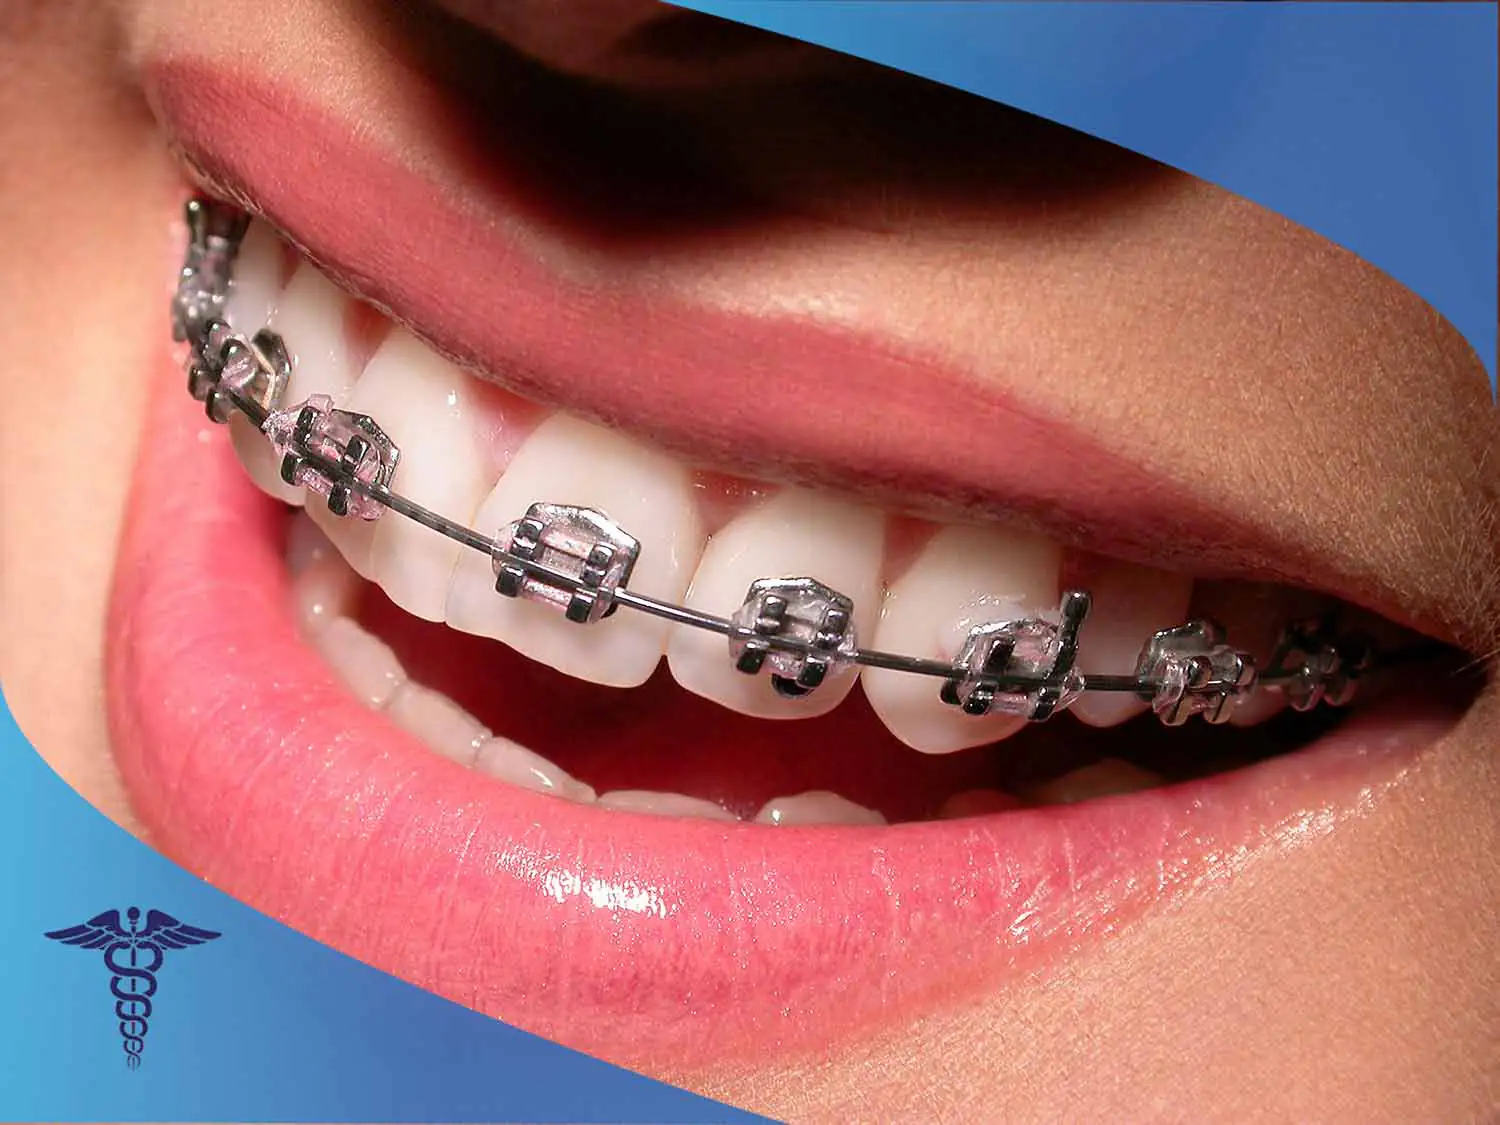

ارتودنسی دندان مدل فلزی

رایج ترین نوع ارتودنسی دندان، ارتودنسی فلزی است که براکت ها به صورت ثابت و بدون هیچ حرکتی روی دندان ها قرار می گیرند. بیمار بدون کمک دندانپزشک قادر به جدا کردن این براکت ها نیست. امکان انتخاب براکت های فلزی با رنگ های متنوع وجود دارد. رعایت بهداشت دهان و دندان و تمیز کردن براکت های فلزی روی ارتودنسی دندان فلزی می تواند از تجمع باکتری ها جلوگیری کند و مانع از پوسیدگی دندان ها شود.

مزایای ارتودنسی ثابت فلزی

- استحکام و مقاومت بسیار بالا

- هزینه قابل قبول نسبت به بعضی از روش های دیگر

- قابل اجرا برای کلیه سنین

- درمان ساده و بدون نگرانی برای بیمار

- قابل استفاده برای انواع ناهنجاری های فک و دندان

معایب ارتودنسی ثابت فلزی

- ظاهر فلزی و مشخص بودن آن روی دندان ها

- اختلال در وضوح تصویربرداری هنگام انجام تصاویر رادیولوژی

- تاثیر روی تکلم

- مشکل حین جویدن غذاها

- عدم رعایت بهداشت دهان و دندان